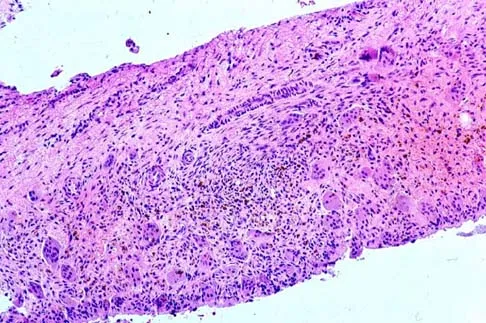

A 16-year-old girl has had pain in the left groin for the past 4 months. She notes that the pain is worse at night; however, she denies any history of trauma and has no constitutional symptoms. There is no history of steroid or alcohol use. Examination reveals pain in the left groin with rotation of the hip. There is no associated soft-tissue mass. A radiograph and MRI scan are shown in Figures 32a and 32b, and biopsy specimens are shown in Figures 32c and 32d. What is the most likely diagnosis?

Explanation

Based on the epiphyseal location and sharp, well-defined borders, the radiograph suggests chondroblastoma. Histologically, multinucleated giant cells are scattered among mononuclear cells. The nuclei are homogenous and contain a characteristic longitudinal groove. Although not seen here, "chicken-wire calcification" with a bland giant cell-rich matrix is also typical for chondroblastoma. Clear cell chondrosarcoma occurs in epiphyseal locations but has a more aggressive histologic pattern and occurs in an older age group. Giant cell tumors occur in the epiphysis but have a more uniform giant cell population histologically. Aneurysmal bone cyst often results in bone remodeling and has a different pathologic appearance. Osteonecrosis has a typical histologic pattern of empty lacunae and necrotic bone. Springfield DS, Capanna R, Gherlinzoni F, et al: Chondroblastoma: A review of seventy cases. J Bone Joint Surg Am 1985;67:748-755. Simon M, Springfield D, et al: Chrondroblastoma: Surgery for Bone and Soft Tissue Tumors. Philadelphia, PA, Lippincott Raven, 1998, p 190.